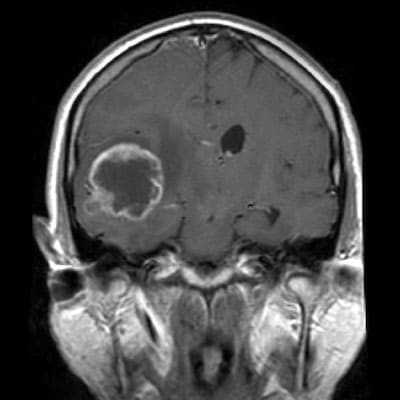

Опухоль головного мозга — глиобластома. Компьютерная томография (КТ). Синяя звездочка в центре обозначает зону центрального некроза опухоли, заполненную жидкостью. Желтые стрелки — окружающий мягкотканный компонент опухоли. Красные звездочки — перифокальный отек мозга. Наблюдается смещение срединных структур и угроза нисходящего транстенториального вклинения мозга.

Проявления опухоли на КТ-сканах без контрастного усиления включают неоднородное образование с нечеткими краями; внутренние области низкой или жидкостной плотности являются очагами некроза (представлены более, чем в 95% МФГ); внутренние области высокой плотности, являющиеся очагами геморрагии или, реже, кальцификациями (они более характерны в тех случаях, когда МФГ является результатом трансформации из астроцитомы низкой степени злокачественности); и значительный масс-эффект и отек (возогенная природа отека).

Исследование КТ с контрастным усилением значительно увеличивает выявление таких признаков, как неровные контуры образрвания, неоднородность, возможное кольцевидное контрастное усиление в периферических отделах патологической зоны.